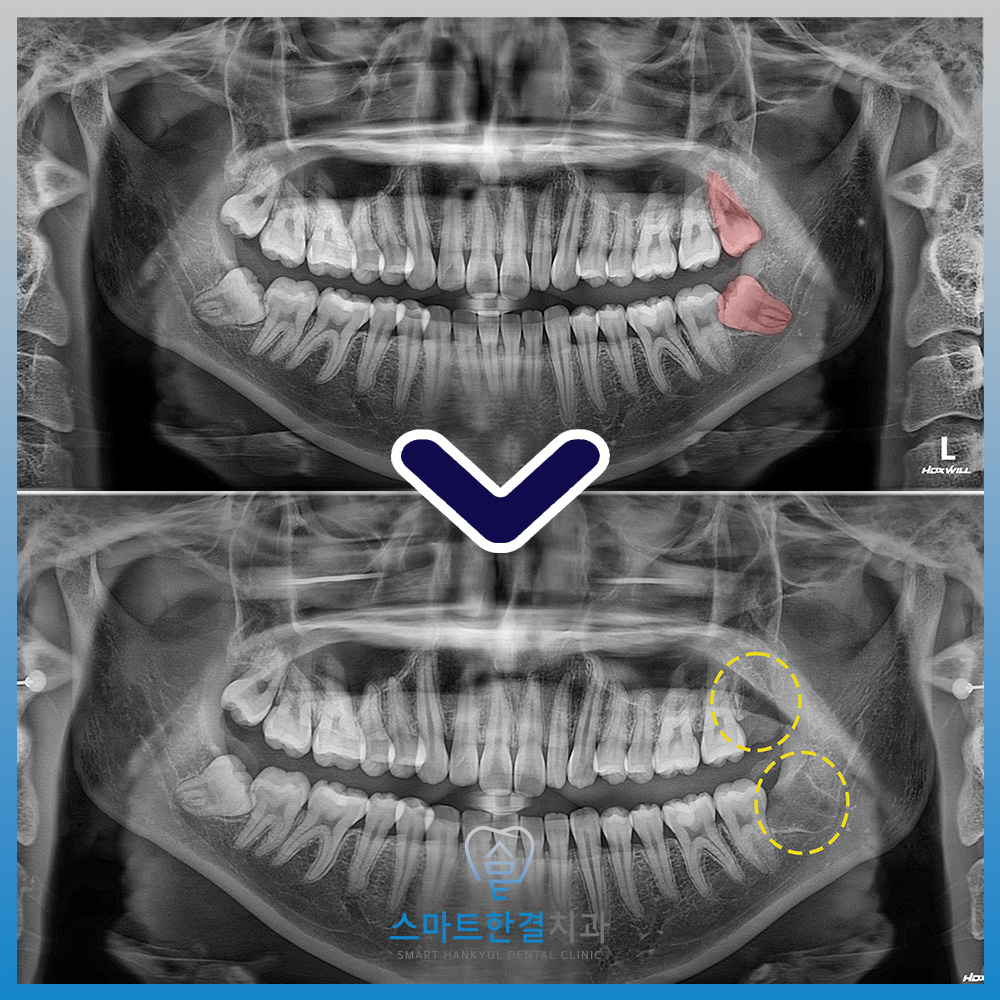

파노라마 사진에서는 왼쪽 아래 사랑니가

잇몸 안에 묻혀 있으면서

앞 치아 쪽으로 비스듬히

누워 있는 모습이 확인되었어요.

왼쪽 위, 아래 2개의

사랑니를 발치한 모습이에요.

잇몸 안으로 매복된 사랑니는 잇몸을 절개하고

치아를 분할한 후 발치하는

수술적 과정이 필요한데요.

수술 중에는 앞 치아에 영향을 주지 않도록

매우 섬세하게 발치를 진행했어요.

또한, 사랑니의 뿌리와 신경관이

파노라마 사진에서 중첩되어 확인되어,

발치 전 3D CT 촬영을 통해 정밀하게 분석한 후

안정적으로 발치를 진행했어요.